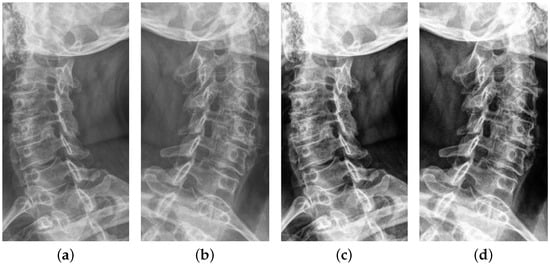

3.1. YOLOv5-Based Region of Interest Detection in X-ray Images

The original oblique view of cervical spine X-ray images includes not only the cervical spine and foramina, which are critical for foraminal stenosis diagnosis, but also additional information, such as teeth, skull, clavicle, and an alphabet indicating left or right view, as shown in Figure 2a,b. Therefore, parts that are not required for foraminal stenosis detection and parts that may be mislearned by the model should be excluded from learning. Therefore, we applied ROI crop to pre-process the input data of the model in this paper. Object detection methods can be applied to detect ROI in the images, i.e., the area of the cervical spine and foramina in the case of cervical spine X-ray images. We used the YOLOv5 [10] model well-known for object detection to obtain ROI-cropped images, as illustrated in Figure 2c,d. In the cervical spine X-ray image, only the cervical spine part was annotated as a bounding box by a clinician. A total of 100 X-ray images were annotated by a clinician and trained the YOLO model using these annotated data. ROI cropping of the other X-ray images (without annotation) was performed by the trained YOLO model. Therefore, the classification model does not intensively learn features other than the cervical spine and foramina. As a result, we separately pre-trained the YOLOv5 model on cervical spine X-ray images and obtained the trained model with the mAP score of 0.97 . The pre-trained YOLOv5 model is applied to all of the raw data and detects the ROI part. The detected ROI part was cropped. The output data of this step, i.e., the ROI crop image, become the input data of the next step, Histogram Equalization, of the proposed model.

Figure 2. Results of ROI crop using YOLOv5. (a) right original oblique view, (b) left original oblique view, (c) right ROI cropped oblique view, and (d) left ROI cropped oblique view.